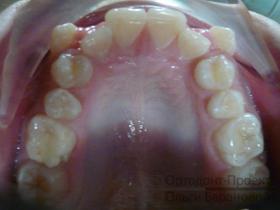

Брекеты Damon установлены:

На текущем этапе ортодонтического лечения использование брекетов сфокусировано на расширении зубного ряда в области второго и четвертого зубов, при этом на системе установлены специальные пружины.

Через пять месяцев начинается новый этап — возвращение клыков на их естественное место в зубном ряду. Вторая дуга обеспечивает стабильное положение передних резцов.